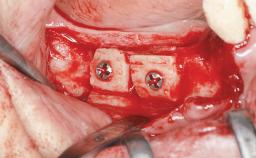

Le Fort I Interpositional Graft and Mandibular Sandwich Osteotomy for Maxillofacial Rehabilitation after Severe Periodontitis

Bone Augmentation Horizontal|Sinus Floor Elevation|Staged|Vertical

Augmentation Materials Autogenous chips|Autogenous block(s)|Xenogenous|Membrane